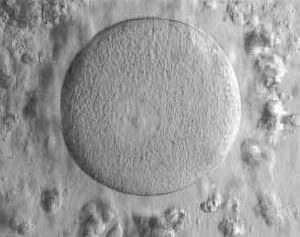

I am a scientist at the University of Manchester and I work several different projects. I am trying new and exciting ways to create Human Embryonic Stem Cells from human eggs (oocytes) that could

possibly be used to help treat diseases like Parkinson’s and diabetes, as well as helping patients with spinal cord injuries (like Superman). As well as this, I look inside very early embryos to see different genes that control their growth and development